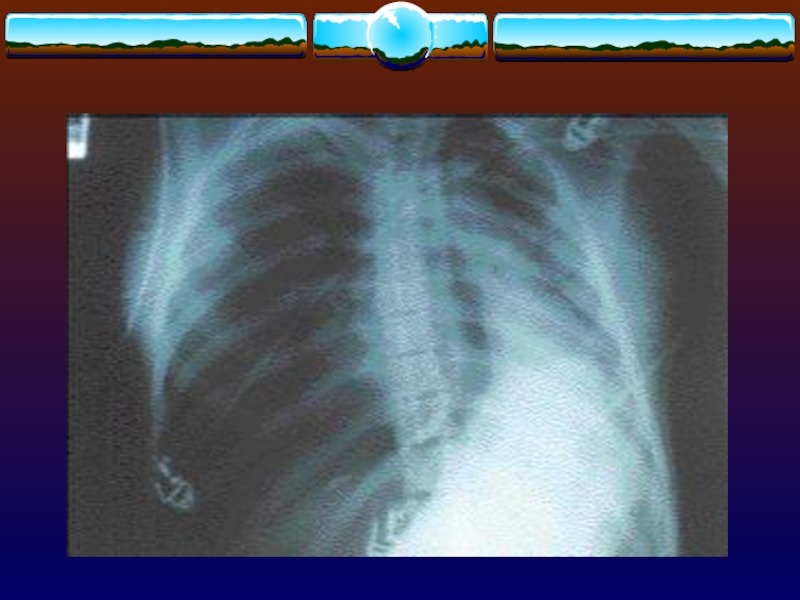

Слайд 6Рентгенография грудной клетки

Проводят, чтобы исключить сопутствующий гемо- или пнемоторакс

В

50% случаепереломы рёбер остаются незамеченными, за исключением переломов верхних рёбер

Используют

косые проекции, что позволяет увеличить информативность метода при диагностике переломов рёбер

При рентгенографии - плотный

лёгочный инфильтрат над поврежденной областью, но определяется только через 12-24

ч после повреждения.

Степень прогрессирования клинических и рентгенологических данных соответствует тяжести поражения.

При КТ диагноз возможно подтвердить раньше, чем при обзорной рентгенография.

Слайд 21Множественный перелом рёбер (I-IX), ключицы, пневмоторакс, подкожная эмфизема слева

Множественный перелом рёбер (I-IX), ключицы, пневмоторакс, подкожная эмфизема слева